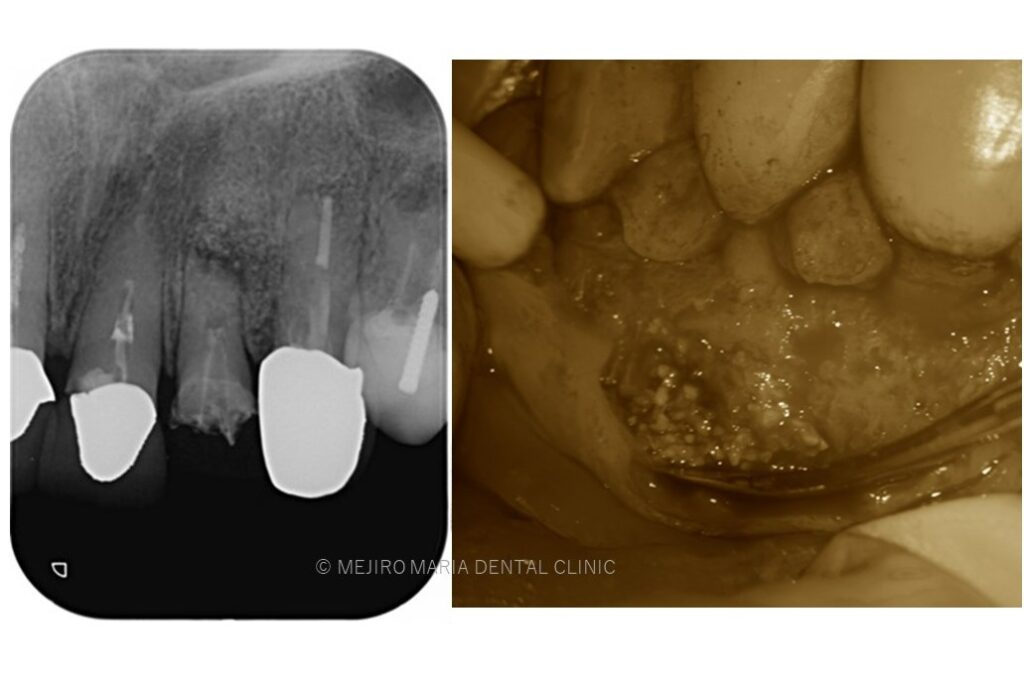

でのリカバリー_感染した人工骨の画像.jpg)

でのリカバリー_治療前の口腔内画像と感染した人工骨の画像-1.jpg)

今回の症例は、他院にて歯根端切除術を行った根尖部(歯の根の先)に充填された人工骨の感染が原因と考えられます。

万が一、歯根端切除術が失敗した場合、人工骨の感染はより事態を悪化させることになります。

歯根端切除術後は術後の透過像で治癒を確認することが重要であり、感染が除去できていれば骨は患者自身の力で自然に再生を行うことになるので、人工骨を充填することはリスクが高い行為であると考えます。